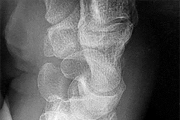

Question 44:

A 62-year-old male of East Asian descent presents with progressive myelopathy. His imaging is shown. Which of the following specific CT findings is the strongest independent predictor of a dural tear during an anterior cervical corpectomy and decompression for this condition?

Explanation:

The image indicates Ossification of the Posterior Longitudinal Ligament (OPLL). The 'double-layer' sign on a CT scan is highly specific for dural ossification and represents a significant risk for dural tears during anterior decompressive surgeries. It consists of anterior and posterior hyperdense ossified rims separated by a central hypodense non-ossified ligament.